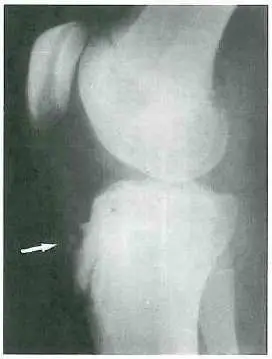

本題圖片為膝關節側位 X 光影像(lateral knee X-ray),影像中有一白色箭頭指向特定部位,可見以下重要發現:

- 箭頭指向脛骨粗隆(tibial tubercle):白色箭頭清楚指向脛骨上端前方的脛骨粗隆部位。

- 脛骨粗隆骨骺不規則:脛骨粗隆骨骺(apophysis)呈現碎裂(fragmentation)或不規則輪廓,骨骺前方可見軟組織腫脹陰影,提示慢性牽引性骨骺炎(traction apophysitis)的影像表現。

- 生長板(growth plate):可見脛骨近端的生長板(骺板),為未成熟骨骼的正常表現,但此部位在 OSD 患者中較易受到股四頭肌牽引力傷害。

- 其他膝關節結構:股骨遠端和脛骨近端關節面看起來正常,無明顯關節積液或腫脹。

影像診斷結論:此影像符合奧斯古德-施拉特病(Osgood-Schlatter disease),即脛骨粗隆骨軟骨炎,為青少年生長期最常見的膝前